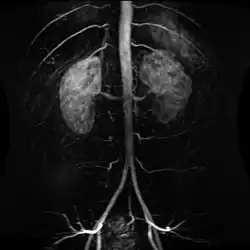

Structure

The abdominal aorta begins at the level of the diaphragm, crossing it via the aortic hiatus, technically behind the diaphragm, at the vertebral level of T12.[1] It travels down the posterior wall of the abdomen, anterior to the vertebral column. It thus follows the curvature of the lumbar vertebrae, that is, convex anteriorly. The peak of this convexity is at the level of the third lumbar vertebra (L3). It runs parallel to the inferior vena cava, which is located just to the right of the abdominal aorta, and becomes smaller in diameter as it gives off branches. This is thought to be due to the large size of its principal branches. At the 11th rib, the diameter is 122mm long and 55mm wide and this is because of the constant pressure.[2] The abdominal aorta is clinically divided into two segments:

1. The suprarenal abdominal or paravisceral segment, inferior to the diaphragm but superior to the renal arteries.

2. The Infrarenal segment, inferior to the renal arteries and superior to the iliac bifurcation.

The abdominal aorta supplies blood to much of the abdominal cavity. It begins at T12 and ends at L4 with its bifurcation into the common iliac arteries[1] and usually has the following branches: